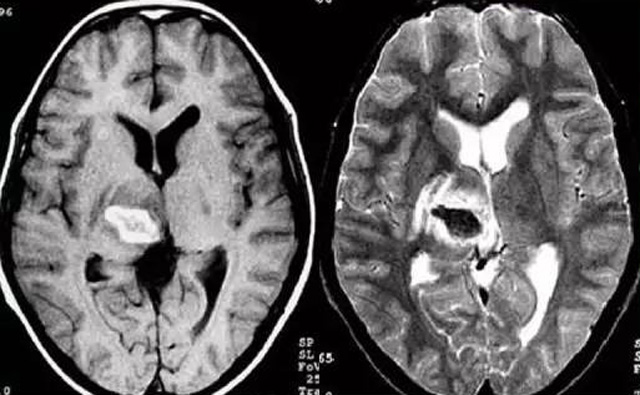

經(jīng)顱多普勒超聲(TCD)磁共振MRI檢查腦出血診斷的作用是什么?

發(fā)現(xiàn)病人出血腦梗相關(guān)癥狀時候第一時間就醫(yī),需要攜帶以往的影像檢查資料。向醫(yī)生提供相關(guān)的病史基本資料。做影像檢查時候需要全身不攜帶金屬物品。檢查時候身體保持不動,不然偽影對檢查結(jié)果有干擾。磁共振MRI發(fā)現(xiàn)缺血性卒中后,幫助進一步查找病因。由于CT上小腦跟腦干顱骨影響,容易導(dǎo)致漏診。MRI檢查可以對CT檢查不足的補充。短暫的腦缺血TIA也需要進行影像檢查。短暫性缺血一般10幾分鐘后好轉(zhuǎn)。檢查目的可以確定TIA的病因。降低腦梗死的發(fā)生率。磁共振有助于排出TIA表現(xiàn)的顱內(nèi)病變,有診斷及時治療的價值。磁共振MRI檢查時間比較長,不太適合急診病人。但是可以發(fā)現(xiàn)腦干小腦的出血問題。因為急性腦梗死的早期和急性期,缺血區(qū)的腦組織還沒有完全壞死,頭顱CT不能顯示病灶,所以就需要MRI磁共振檢查,這個對陳舊跟亞急性出血顯示比較好。缺點性價比不高,費用比較貴。頭顱的磁共振MRI在發(fā)病后的幾天CT的敏感降低時候發(fā)揮大作用。,MRI可作為診斷蛛網(wǎng)膜下腔出血和了解破裂動脈瘤部位的一種重要方法,必要時進一步進行DSA檢查,幫助制訂臨床的手術(shù)治療方案,

經(jīng)顱多普勒超聲(TCD)有效沒有創(chuàng)傷性的檢查方法,是檢查腦血管的設(shè)備之一,它目前廣泛應(yīng)用于臨床,檢查判斷腦出血卒中的頭顱里面的內(nèi)動脈外動脈的病變問題。診斷顱內(nèi)動脈狹窄或閉塞性病變。顱外頸部動脈狹窄或閉塞性病變,評價顱外動脈嚴重狹窄或閉塞對顱內(nèi)血流速度的影響。頸動脈內(nèi)膜剝脫手術(shù)前預(yù)測夾閉作用、術(shù)后評估顱內(nèi)血流變化。